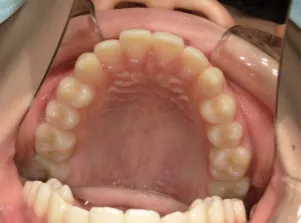

治療前①小2:8y1m 初診

| カウンセリング・診断結果 | 前歯が受け口になっていているため、適正な成長へ誘導するために前歯の咬み合わせの改善が必要なことを説明し、診断を希望されたので精密検査へ進みました。 精密検査の結果、骨格的には受け口傾向、下顎前歯の突出、上下ともアーチが小さく凸凹(叢生)が認められ、機能的には低位舌と口唇閉鎖不全があり、口元は上下唇とも突出していますがコンケーブになってないことがわかりました。 |